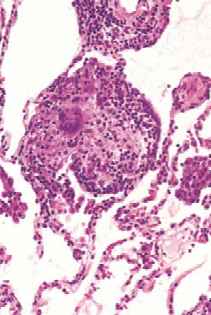

Sarcoidosis

Cuerpos asteroides

Cuerpos de Schaumann